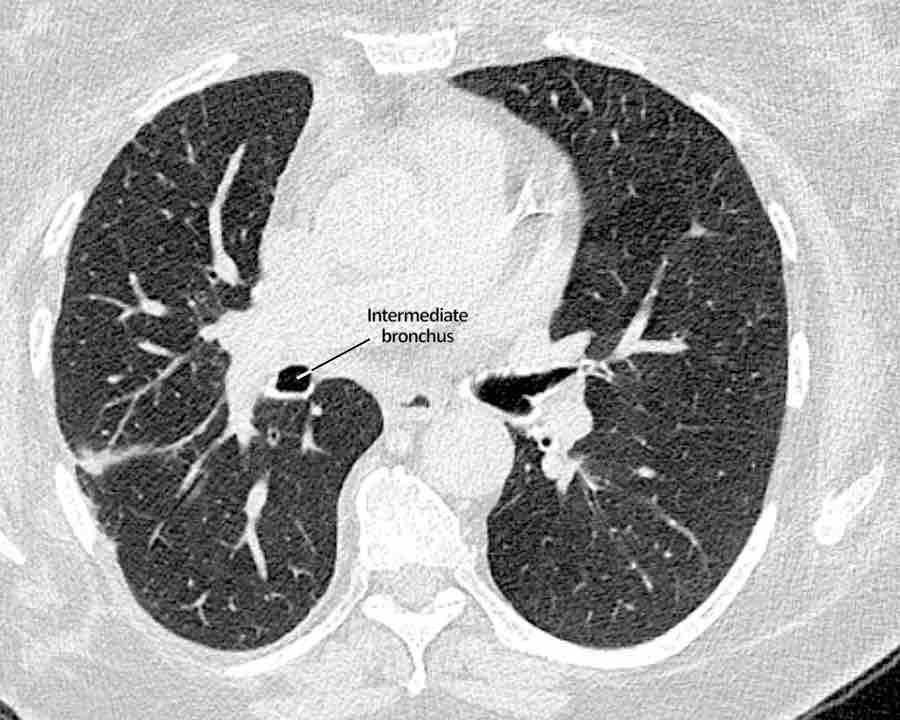

Phế quản trên CT

Cuộn qua các hình ảnh để quan sát khí quản phân chia thành phế quản chính phải và trái, sau đó tiếp tục phân chia thành các phế quản thùy và phế quản phân thùy.

Phế quản thùy trên, phế quản trung gian và phế quản thùy dưới tiếp tục đi về phía ngoại vi.